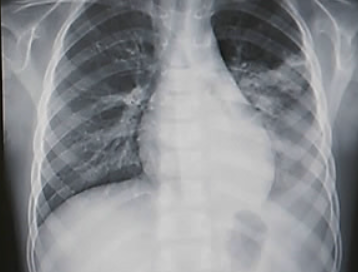

겨울철과 환절기 건강을 위협하는 가장 위험한 질환 중 하나인 폐렴입니다.

폐렴은 초기 증상이 감기나 독감과 비슷해 방치하기 쉽지만, 노년층에게는 치명적일 수 있습니다.

38.3도 이상의 고열, 화농성(누런색) 가래를 동반한 기침, 가슴 통증, 호흡 곤란 등이 나타납니다.